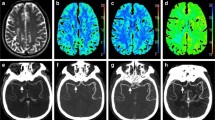

Table 3 summarizes the agreement and accuracy of classifying CTP diagnostic criteria with dCTP and mCTA-P. Forty-six patients had a favourable mismatch profile as determined by standard CTP. A substantial agreement (κ = 0.75, 95% confidence interval [CI]: 0.56–0.94) was found between CTP and dCTP mismatch profiles whereas agreement was moderate with mCTA-P (κ = 0.48, 95% CI: 0.22–0.74). Using CTP mismatch profiles as the ground truth, classification accuracy was 90% with dCTP and 82% with mCTA-P. Overall, mCTA-P had weaker specificity for identifying an unfavourable mismatch than sensitivity for a favourable profile. Figures 3 and 4 show examples of a concordant and discordant mismatch profile using mCTA-P versus CTP.

Patient presenting with unknown time from stroke symptom onset, a bilateral occlusion of the right M2 middle cerebral artery (MCA) and left distal posterior cerebral artery (PCA), and an NIHSS of 10. This patient received endovascular thrombectomy for the right M2 occlusion within 53 min of admission CT (mTICI = 3), but the posterior occlusion could not be treated. (A.i) Admission non-contrast CT; (A.ii) maximum intensity projections of CT angiography with the red circle indicating the occlusion site; (A.iii) follow-up diffusion-weighted imaging showing regions of infarction in the right M2 territory (red arrows) and the left posterior brain (red outline). (B.i) CT perfusion ischemic core (red, 19.4 ml) and penumbra (green, 45.5 ml; mismatch ratio of 2.3) derived from cerebral blood flow (B.ii) and Tmax maps (B.iii) indicated a favourable DEFUSE-3 mismatch profile. (C) Similarly, down-sampled CT perfusion (dCTP) indicated a favourable mismatch profile with an ischemic core and penumbral volumes of 4.8 ml and 26.9 ml, respectively (mismatch ratio 5.6). (D) Multiphase CT angiography-perfusion (mCTA-P) agreed with the favourable CTP mismatch profile with ischemic core and penumbral volumes of 1.2 ml and 51.2 ml, respectively (mismatch ratio 44.3). Of note, the indicated lesion volumes were only of the right MCA territory so that the left PCA lesion volumes did not affect the estimation of mismatch.

Patient presenting 5 h after stroke symptom onset with an occlusion of the right internal carotid to M1 middle cerebral artery and an NIHSS of 22. This patient did not receive reperfusion treatment. (A.i) Admission non-contrast CT shows early ischemic changes in the right MCA territory; (A.ii) maximum intensity projections of CT angiography with the red arrow indicating the occlusion site; (A.iii) follow-up non-contrast CT showing infarction and hemorrhage outlined in red. (B.i) CT perfusion ischemic core (red, 84.0 ml) and penumbra (green, 236.8 ml; mismatch ratio of 2.8) derived from cerebral blood flow (B.ii) and Tmax maps (B.iii). DEFUSE-3 mismatch was unfavourable by CT perfusion due to the large core volume. (C) Similarly, down-sampled CT perfusion (dCTP) indicated an unfavourable mismatch profile with an ischemic core and penumbral volumes of 71.7 ml and 205.3 ml, respectively (mismatch ratio 2.9). (D) Multiphase CT angiography-perfusion (mCTA-P) showed a similar ischemic lesion, but underestimated ischemic core and penumbra at 58.0 ml and 202.5 ml, respectively (mismatch ratio 3.5), leading to a favourable DEFUSE-3 mismatch profile and disagreement with CTP.